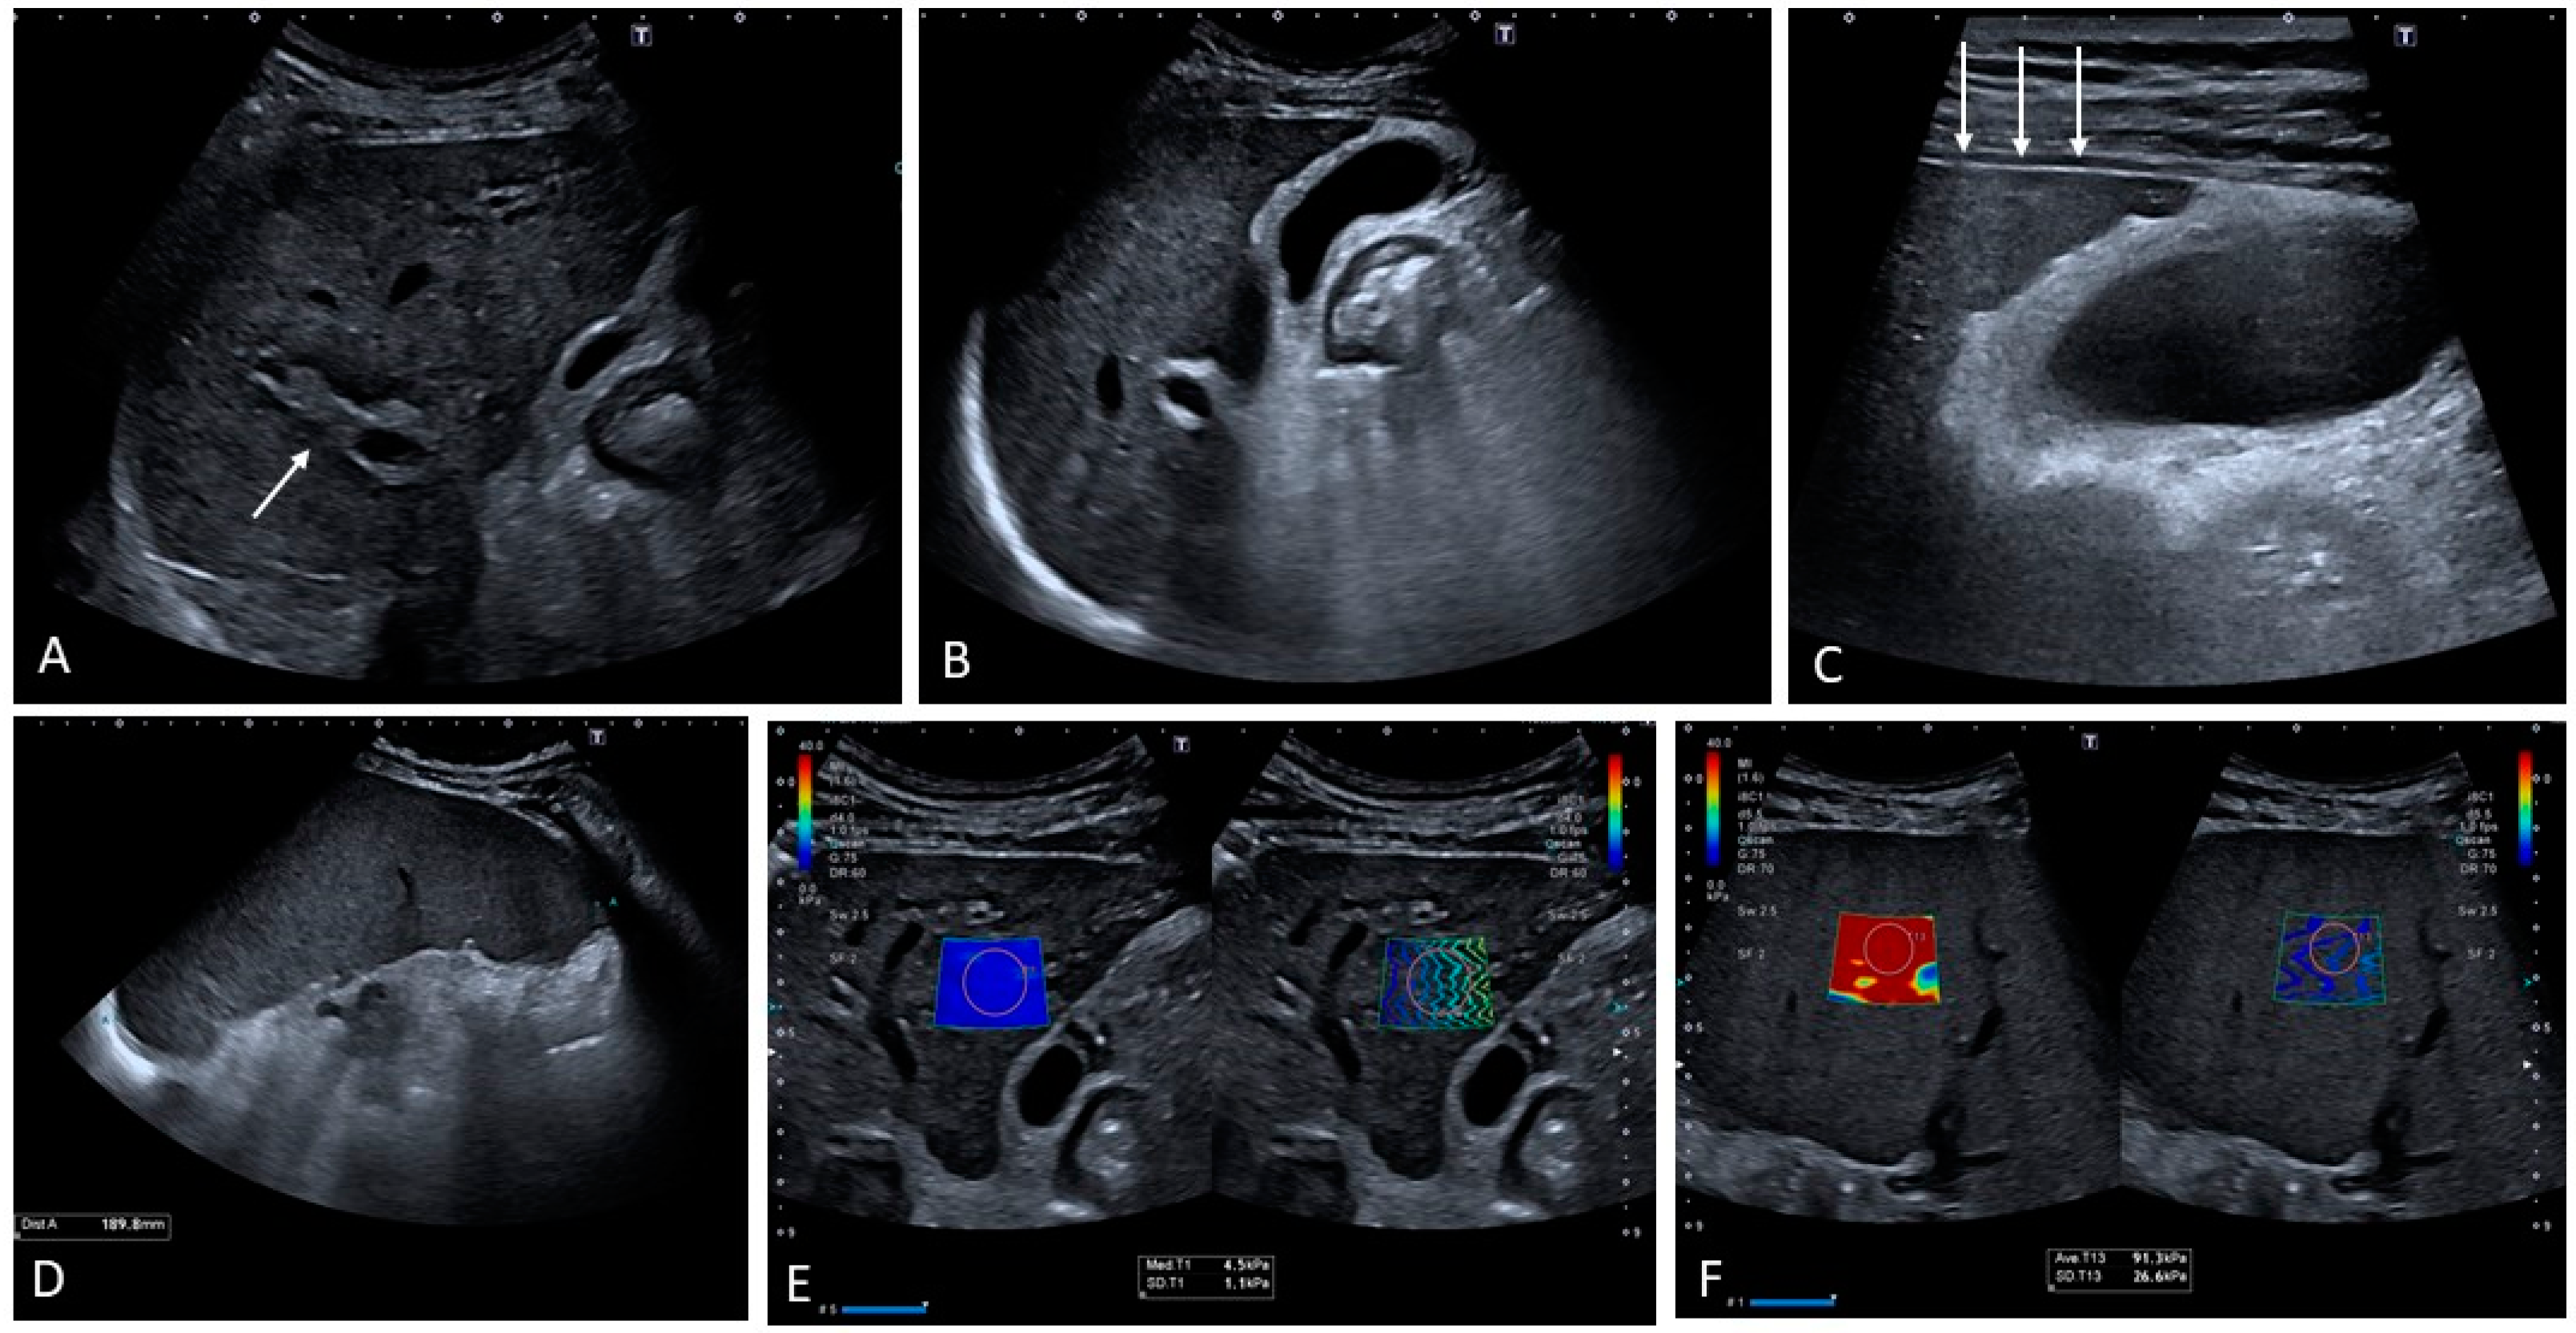

4.2. Sinusoidal Obstruction Syndrome

- Bohte, A.E.; Dierselhuis, M.P.; van Noesel, M.M.; Lequin, M.H. Imaging features of hepatic sinusoidal obstruction syndrome or veno-occlusive disease in children. Pediatr. Radiol. 2022, 52, 122–133. [Google Scholar] [CrossRef]

- Zhang, Y.; Yan, Y.; Song, B. Noninvasive imaging diagnosis of sinusoidal obstruction syndrome: A pictorial review. Insights Imaging 2019, 10, 110. [Google Scholar] [CrossRef] [PubMed]

- Chan, S.S.; Colecchia, A.; Duarte, R.F.; Bonifazi, F.; Ravaioli, F.; Bourhis, J.H. Imaging in Hepatic Veno-Occlusive Disease/Sinusoidal Obstruction Syndrome. Biol. Blood Marrow Transplant. 2020, 26, 1770–1779. [Google Scholar] [CrossRef] [PubMed]

- Ravaioli, F.; Colecchia, A.; Alemanni, L.V.; Vestito, A.; Dajti, E.; Marasco, G.; Sessa, M.; Pession, A.; Bonifazi, F.; Festi, D. Role of imaging techniques in liver veno-occlusive disease diagnosis: Recent advances and literature review. Expert Rev. Gastroenterol. Hepatol. 2019, 13, 463–484. [Google Scholar] [CrossRef] [PubMed]